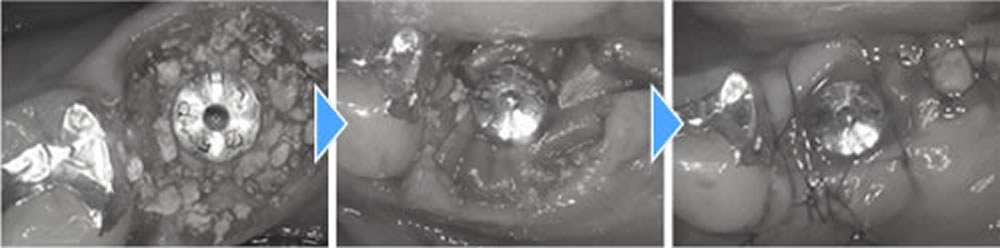

まず歯を抜き、中の膿を綺麗に取り除いた後に即時でインプラントを埋入し、骨の無くなってしまっている場所に骨造成を行いました。こちらは減張切開を行い、創の完全閉鎖をしました。

1つ前の歯も抜歯後に中を綺麗にし、インプラント埋入、骨造成までを1度のオペで行っていきました。こちらはインプラントの蓋が外に出るような形にして縫合しました。